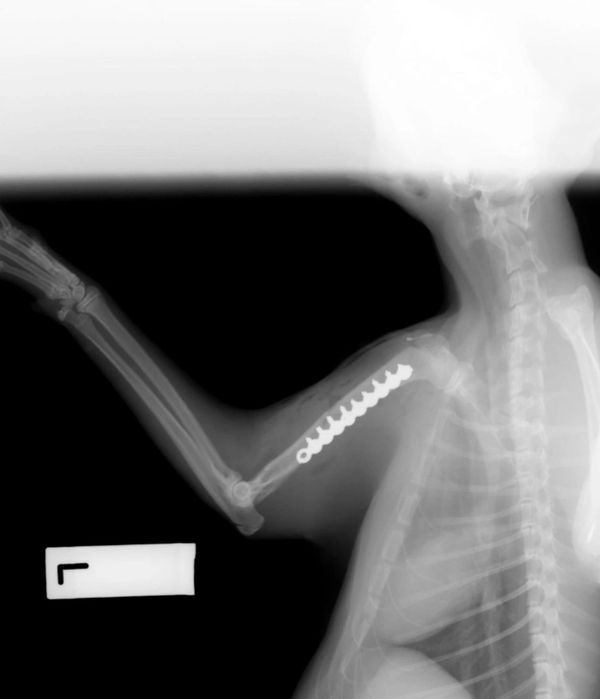

We rescued 'Soldier Boy' from the Pound recently and booked him in for Desex, Microchip and Vaccination.

During his consultation with the Vet, a nurse discovered that 'Soldier Boy' was unhappy about having his 'Left Shoulder/Leg' touched.

After further investigation under Anaesthetic... a Bullet was removed from his shoulder.

It appears that a heartless individual had shot at him.

We were absolutely mortified upon hearing this news... and unfortunately this isn't the first Bullet that Vets have removed from a cat we have rescued.